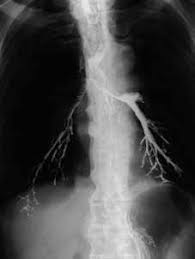

胃のバリウム検査で稀に誤嚥してしまうことがあります。

誤嚥してしまうとバリウムが肺にとどまることになり肺の検査で

バリウムが肺に写ってしまいます。

ですからバリウム検査を受ける時、咳が出ていないか、飲み込む時、咽せることがないか確認しています。

もし該当するのであれば胃カメラに変更していただくと良いかもしれません。

↑バリウム誤嚥の参照画像